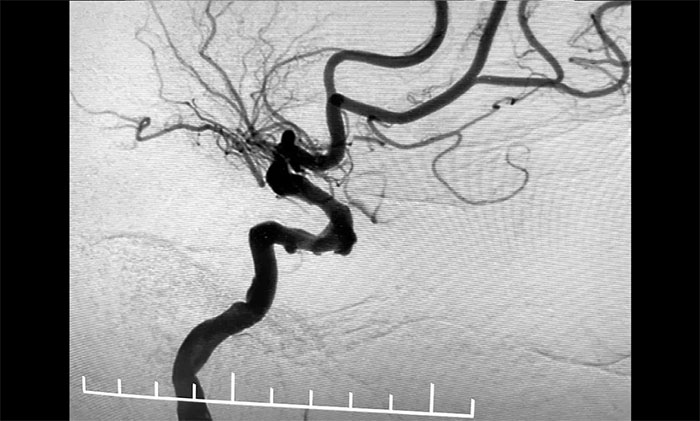

▲ 颈动脉狭窄合并左颈内动脉海绵窦段、床突段多发动脉瘤

接下来,左颈内动脉海绵窦段、床突段多发动脉瘤处理极具挑战。由于C5、C6、C7段血管极度迂回曲折,类似“N”形,从C4、C5到C6之间的血管约成45°锐角,从C6至C7之间又是约30°锐角,可谓“山路十八弯”,而导丝又是极软,每向前推进一毫米,都非常艰难。这种介入手术对术者的技术要求非常高,如果支架贴合不好,打开不良,还需要用导丝蠕动“按摩”,让支架重新回到血管壁上。

术中,席刚明教授、王贵平博士克服血管迂曲困难,经过多次尝试,多次球囊扩张、“按摩”后,最终顺利释放密网支架至左颈内动脉眼动脉段、左颈内动脉床突段、左颈内动脉海绵窦段。造影及3D造影见,动脉瘤瘤内造影剂明显滞留,左颈内动脉、左大脑前动脉显影可,载瘤动脉通畅,获得了理想的血管重建。复查造影,左颈总动脉造影见左颈总动脉、左颈内动脉、左大脑前动脉显影可。CT见支架打开贴壁满意,XperCT未见颅内出血,手术圆满完成,顺利拆除“不定时炸弹”并打通大脑生命线。

▲ 血管极度迂曲,为手术带来挑战